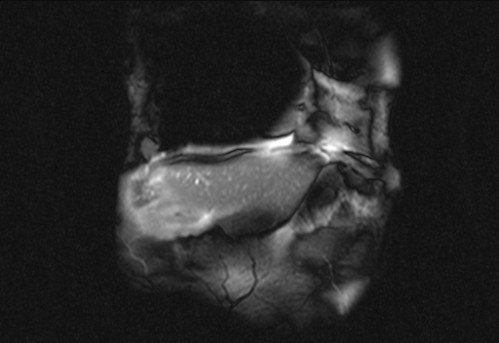

Auffälliges Abdomen bei der Vorsorgeuntersuchung einer älteren Dame

ICD: C64

68 Jahre alte Frau. Sie geht zur Darmspiegelung im Rahmen ihrer Krebsvorsorgeuntersuchung. Der Internist bemerkt bei der ergänzenden sonografischen Untersuchung des Abdomens einen auffälligen Befund.